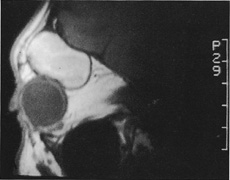

Magnetic resonance imaging is useful in selected cases, especially when evaluating the orbital cranial junction. Significant bony artifact and a lack of orbital fat in the orbital apex make CT scan resolution of the orbital apex structures poor. Because cortical bone has low signal on MRI, there is no bone artifact when viewing the orbital apex on MRI. The lack of intervening fat in the apex to provide contrast is overcome on MRI because contrast is provided by the individual nuclear characteristics of each tissue so that the orbital apex structures are visualized well. Consequently, conditions that affect the optic nerve and chiasm, such as optic nerve meningioma and glioma, generally are evaluated with MRI rather than CT scan (Fig. 2).

Fig. 2. A. Axial orbital CT scan of right optic nerve meningioma. Note lack of detail in orbital apex. B. Axial orbital MR image, same patient. Note increased detail in orbital apex owing to lack of bone artifact. C. MRI with gadolinium contrast. Note extension into brain not easily appreciated with CT scanning or MRI without contrast.